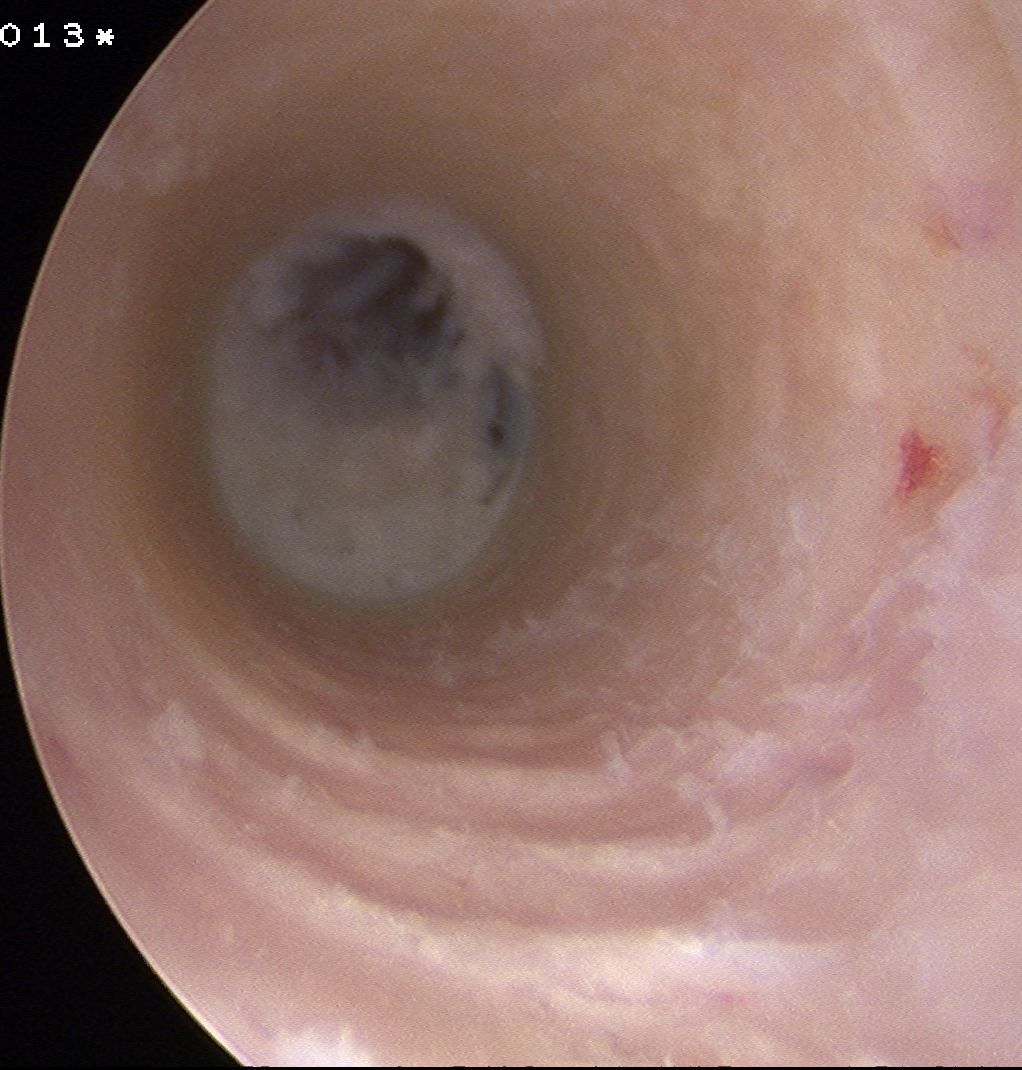

Achilles allograft used, and 12 mm x 20 mm bone plug used in femoral side. Both tunnels drilled where indicated.

Tibial screw ignored, old femoral tunnel ignored. 12 mm tunnels drilled.

Old staple had to be removed. Graft passed and fixed on femoral side with 9 x 25 mm screw.

Achilles tendon fixed on tibial side with 9 x 25 screw